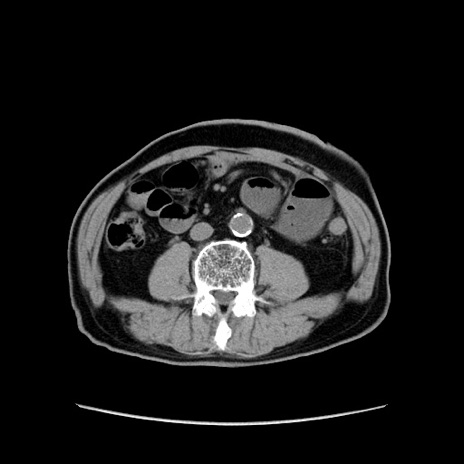

冠状断像